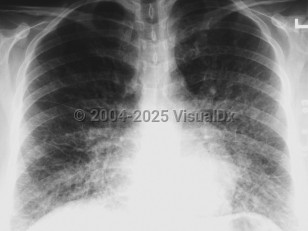

The incubation period for HCPS is 1-6 weeks but usually lasts for 2 weeks. Initial symptoms include the sudden onset of 3-5 days of fever, dry cough, fatigue, dizziness, myalgia, headaches, chills, nausea, vomiting, and abdominal complaints. The gastrointestinal symptoms can at times be severe and mimic surgical emergencies such as appendicitis, cholecystitis, or diverticulitis. Arthralgias and back pain occur less frequently. The disease progresses rapidly to fever, severe coughing, dyspnea, tachypnea, tachycardia, rales, diffuse pulmonary edema, acute respiratory distress syndrome (ARDS), and death. Rarely, some patients may develop disseminated intravascular coagulation (DIC). At the time most patients seek medical care, they usually require immediate intubation and mechanical ventilation.